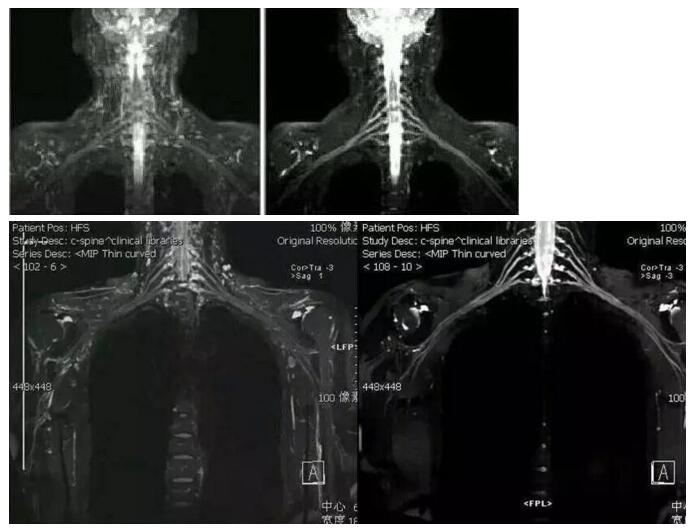

左圖為改進(jìn)前的圖像,右圖為新技術(shù)的圖像

由我院醫(yī)學(xué)影像中心經(jīng)過(guò)多次討論出來(lái)的新方案做出來(lái)的新圖像,相比之前的技術(shù),新方案的圖像幾乎沒(méi)有受到的背景信號(hào)干擾。

磁共振成像新技術(shù)做出來(lái)的圖像可清晰地顯示臂叢神經(jīng)全貌及周圍組織結(jié)構(gòu)關(guān)系,能顯示神經(jīng)根的撕裂,還能同時(shí)顯示合并存在的脊膜膨出、腦脊液外漏、脊髓出血、水腫等。

而且 磁共振水成像技術(shù)對(duì)顯示蛛網(wǎng)膜下隙及腦脊液的外漏更為清楚。在臂叢神經(jīng)病變的診斷中起有不可磨滅的作用。

根據(jù)檢查所作圖像重建的三維圖像,我們可以從各個(gè)方位觀察臂叢神經(jīng)